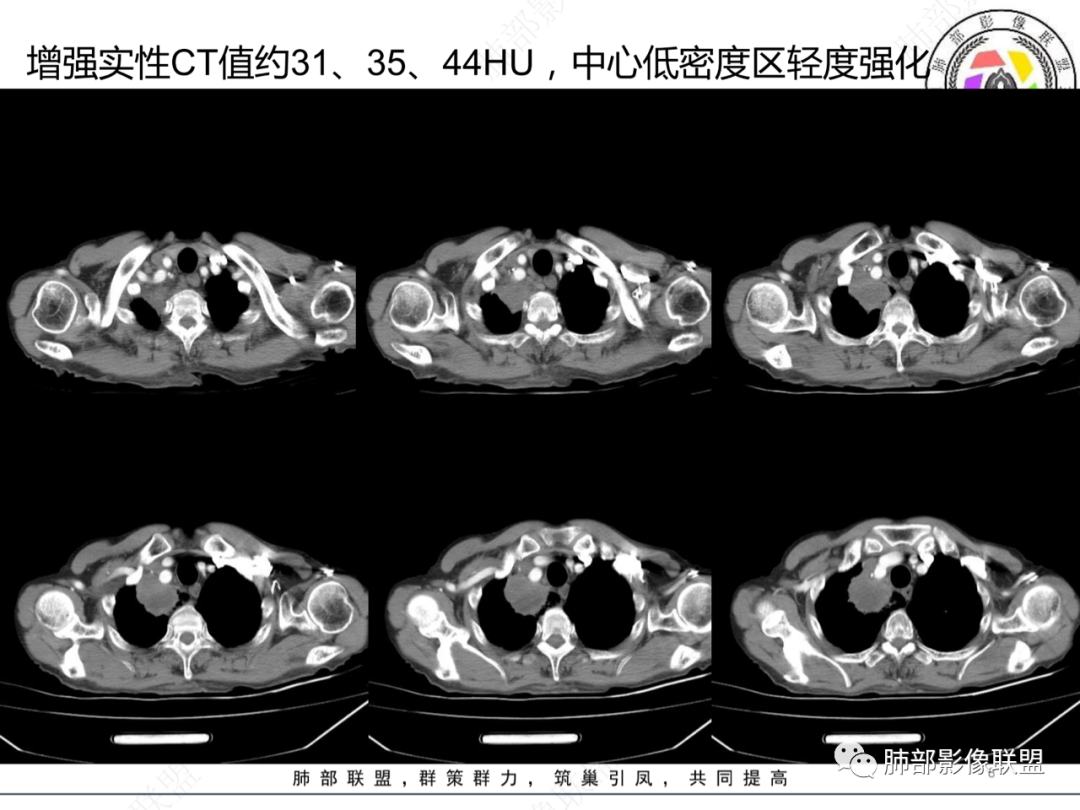

体温39度,白细胞显著升高。右肺上叶团块,边缘毛糙,其内近心侧大面积液化坏死,病灶相近内侧肺内见淡片影,增强渐进式轻度强化,坏死边缘较清晰。纵隔2组及4组淋巴结环形强化,边界清晰无融合,与肺病灶同源。一月后复查病灶出现破溃形成气液平,周围渗出,胸腔积液。先考虑感染性病变,结核,脓肿。恶性病变待排。

右肺上叶肿块,其内见液化坏死,增强实性部分明显强化,坏死边缘较清晰,纵隔淋巴结环形强化,与肺内病灶相似;一月后复查形成气液平,周围渗出,胸腔积液;考虑感染性病变,结核、脓肿,不除外鳞癌合并感染

秦化君 :